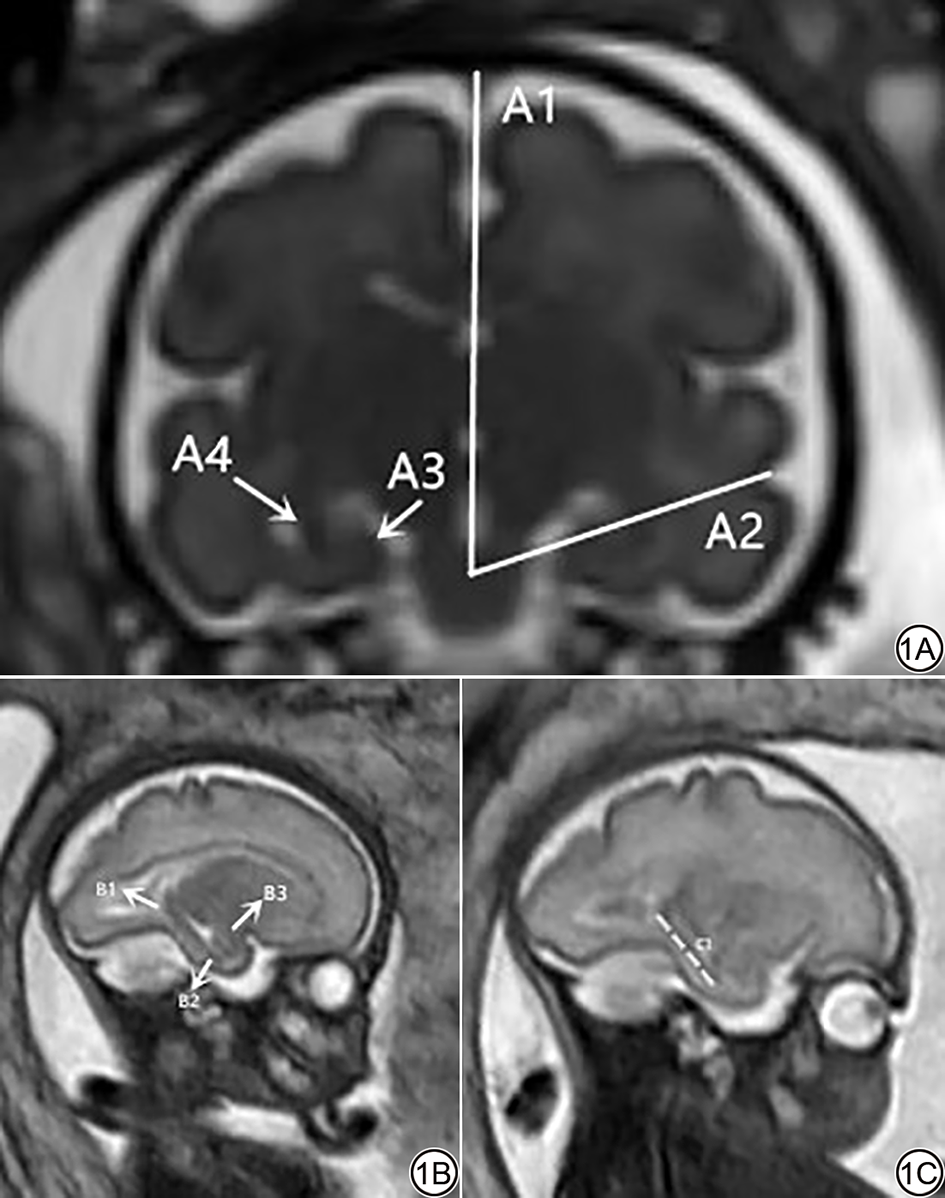

将原始MRI图像传至PACS系统,在矢状位SSh-TSE序列上测量胎儿左右海马长径,在有杏仁核层面测量海马尾后上缘到海马头前下缘的距离。在冠状位BTFE序列上测量左右两侧HIA,在有脑桥显示的图像上测量,角度的两条射线分别为连接海马下托内侧面上缘与海马角的外侧缘连线以及大脑半球垂直中线,图像的测量由2名具有5年以上工作经验的放射诊断医生独立审查图像并进行测量,取平均值,在测量完成前,医生对临床资料以及分组情况不知情。采用组内相关系数(intra-class correlation coefficient, ICC)评估两名测量者间结果的一致性,两名测量者对双侧海马长径、HIA角测量结果的一致性信度优秀(左侧海马长径ICC=0.983,95% CI:0.974~0.988,P<0.001;右侧海马长径ICC=0.980,95% CI:0.970~0.986,P<0.001;左侧海马折叠角ICC=0.982,95% CI:0.954~0.991,P<0.001;右侧海马折叠角ICC=0.982,95% CI:0.970~0.989,P<0.001),ICC值的解释依据Koo & Li(2016)[14] 的标准:<0.50表示一致性差;0.50<0.75表示一致性中等;0.75<0.90表示一致性良好,>0.90表示一致性优秀。测量方法见图1

图1  孕30周 IUGR胎儿。1A:BTFE序列冠状位示意图,A1为大脑半球垂直中线,A2为海马托内侧面上缘与海马角外侧缘连线,A3(箭)为海马托内侧面上缘,A4(箭)为海马角外侧缘;1B:SSh-TSE序列矢状位示意图,B1(箭)为右侧海马尾,B2(箭)为右侧海马头,B3(箭)为杏仁核;1C:SSh-TSE序列矢状位示意图,C1(虚线)为左侧海马尾后上缘到海马头前下缘的距离。IUGR:宫内生长发育受限。

Fig. 1  Fetus with IUGR at 30 weeks of gestation. 1A: Coronal view schematic diagram of BTFE sequence, A1 is the vertical midline of the cerebral hemisphere, A2 is the line connecting the upper edge of the medial superior margin of the subiculum and the lateral margin of the cornuammonis, A3 is medial superior margin of the subiculum, A4 is he lateral margin of the cornuammonis; 1B: Sagittal view schematic diagram of SSh-TSE sequence, B1 is the right hippocampal tail, B2 is the right hippocampal head, B3 is the amygdala; 1C: Sagittal view schematic diagram of SSh-TSE sequence, C1 is the distance from the posterior superior edge of the left hippocampal tail to the anterior inferior edge of the hippocampal head. IUGR: intrauterine growth restriction.